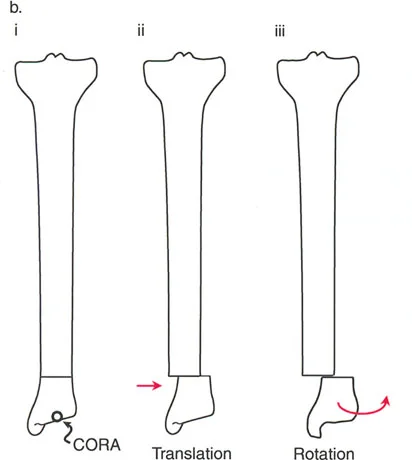

- الدوران (Rotation): عندما يدور العظم حول محوره الطولي، مما يؤثر على اتجاه القدم أو الركبة.

- الترجمة (Translation): عندما ينزاح جزء من العظم جانبيًا بالنسبة للجزء الآخر.

- قاعدة قطع العظم 1: عندما يمر قطع العظم ومحور تصحيح الانحراف (ACA) كلاهما عبر مركز دوران الانحراف (CORA)، فإن نهايات العظم ستنحرف دون ترجمة (انزياح). يتم استعادة المحور الميكانيكي، وتظل نهايات العظم متقاربة تمامًا، مما يخلق تصحيحًا كلاسيكيًا "إسفينيًا مفتوحًا" أو "إسفينيًا مغلقًا".

- قاعدة قطع العظم 2: عندما يمر محور تصحيح الانحراف (ACA) عبر مركز دوران الانحراف (CORA)، ولكن يتم إجراء قطع العظم على مستوى مختلف (غالبًا بسبب ضعف جودة العظم عند CORA أو مشاكل في الجلد)، فإن نهايات العظم ستنحرف وتخضع لترجمة محسوبة ومقصودة لإعادة محاذاة المحور الميكانيكي.

- قاعدة قطع العظم 3: (للاكمال) عندما يمر قطع العظم عبر مركز دوران الانحراف (CORA)، ولكن يتم وضع محور تصحيح الانحراف (ACA) خارج CORA، سيتم إنشاء تشوه ترجمة جديد، وهو خطأ شائع في وضع المفصلات غير المخطط له جيدًا.